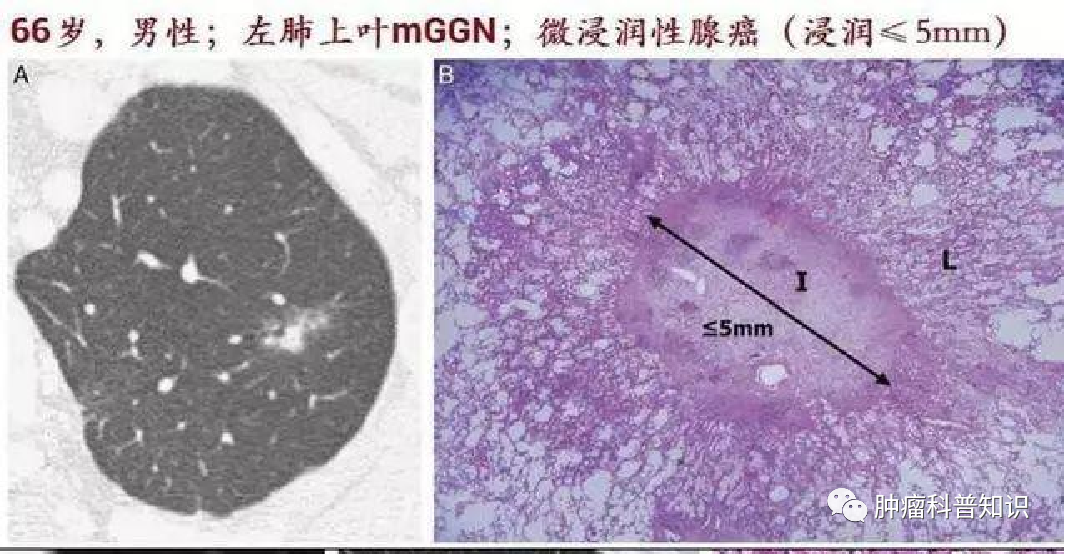

微浸润腺癌(MIA)

是原位癌的进一步发展,不超过5mm的浸润,如果没有得到及时的治疗,癌细胞就会继续发展,穿破基底层,发展成为微浸润腺癌,有转移和扩散的能力。